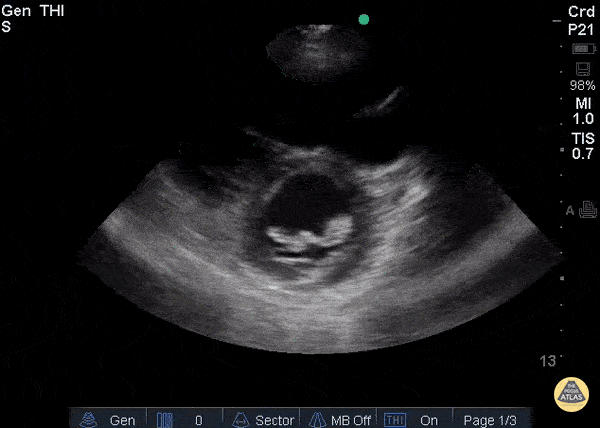

Valvulopathy - Endocarditis PSAX

Patient with history of IV drug use, admitted for sepsis. Parasternal short axis view shows large mass attached to anterior leaflet of mitral valve. Blood cultures prove bacterial endocarditis. Ria Dancel, MD. University of North Carolina at Chapel Hill